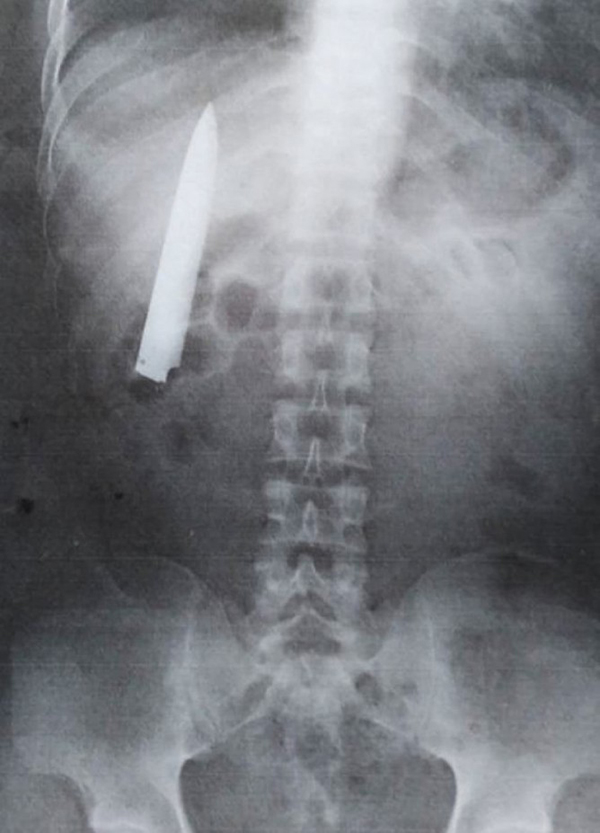

எக்ஸ் ரே………….

பிலிப்பைன்சில் சுரங்க வேலையில் சேர்வதற்காக மருத்துவ பரிசோதனைக்கு சென்ற இளைஞர், எக்ஸ் ரே செய்து பார்த்த போது, அவருக்கும் பெரும் அதிர்ச்சி காத்திருந்தது. கடந்த ஆண்டு, ஜனவரி மாதம் பிலிப்பைன்சின் Kidapawan நகரில் வேலை முடிந்து வீட்டிற்கு செல்லும் போது, Kent Ryan Tomao என்ற 36 வயது நபர் கத்தி காயத்தால் பாதிக்கப்பட்டார்.

இதையடுத்து அவர் உடனடியாக அருகில் இருக்கும் மருத்துவமனைக்கு கொண்டு செல்லப்பட்டார். அங்கு மருத்துவர்கள் அவருக்கு சிகிச்சையளித்து, வலி நிவாரணி மாத்திரைகளை கொடுத்துள்ளனர்.

அதன் பின் வழக்கம் போல் இருந்த Kent Ryan Tomao சுரங்க வேலை ஒன்றில் சேர்வதற்காக சென்றுள்ளார். அப்போது அவரின் உடல்நிலை எப்படி இருக்கிறது என்பது குறித்த சான்றிதழ் வேண்டும் என்று அங்கு கேட்டுள்ளனர்.

இதனால், அவர் மருத்துவபரிசோதனைக்காக அங்கிருக்கும் மருத்துவமனைக்கு சென்றுள்ளார். அப்போது அவருக்கு ஸ்கேன் செய்து பார்த்த போது, அவரது விலா எலும்புக் கூண்டுக்கு அருகிலும், நுரையீரலை துளைப்பதில் ஒரு அங்குலம் இடைவெளி விட்ட நிலையில், கூர்மையான கத்தி இருப்பதைக் கண்டு மருத்துவர்கள் அதிர்ச்சியடைந்துள்ளனர்.

அவர் அந்த கத்தியை உடலில் இருந்து அகற்றும் வரை, சுரங்க வேலைக்கு செல்ல முடியாது. அப்போது ஏற்பட்ட காயத்தை மருத்துவர்கள் சரியாக பார்க்காததால், இப்போது அதன் உண்மை தெரியவந்துள்ளது.

இது குறித்து அந்த நபர் கூறுகையில், குளிர்ச்சி காலங்களில் என்னுடைய மார்பில் வலி ஏற்படும். ஆனால் அது அந்தளவிற்கு பெரிதாக இருக்காது. நான் வலி நின்றவுடன் மீண்டும் பழைய படி வேலை செய்ய துவங்கிவிடுவேன்.

இதை நான் பெரிதாக எடுத்து கொள்ளவில்லை. இப்போது அதன் உண்மையான பிரச்சனை என்பதை அறிந்து கொண்டேன். எனக்கு கடந்த ஆண்டு சிகிச்சையளித்து மருத்துவமனை நிர்வாகம் மீது நடவடிக்கை எடுக்க எந்த திட்டமும் இல்லை. உடல் நிலை சரியாகினால் போதும், அப்போது தான் நான் வேலைக்கு செல்ல முடியும் என்று கூறியுள்ளார். இதற்கான சிகிச்சைக்காக அவர் முறையாக அடுத்த மாதம் வரை காத்திருக்க வேண்டும் என்று கூறப்படுகிறது.